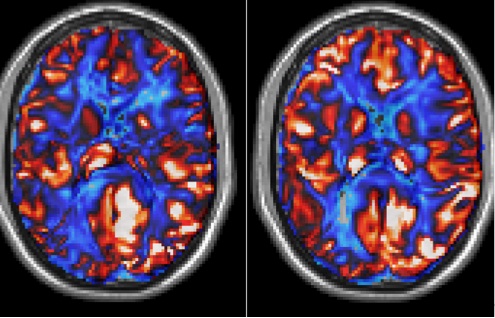

Strategy-based cognitive training has the potential to reverse age-related brain decline according to the results of a study conducted by researchers at the Center for BrainHealth at The University of Texas at Dallas published online in Cerebral Cortex. The novel study examining brain and cognitive changes associated with brain training has found that complex cognitive training significantly improves cognitive brain health.“The world’s aging population is growing disproportionately. Our expected lifespan has reached an all time high of more than 78 years, yet previous research shows cognitive decline may begin in the early 40s,” said Dr. Sandra Bond Chapman, founder and chief director of the Center for BrainHeath and Dee Wyly Distinguished University Chair at The University of Texas at Dallas. “Until recently, cognitive decline in healthy adults was viewed as an inevitable consequence of aging. This research shows that neuroplasticity can be harnessed to enhance brain performance and provides hope for individuals to improve their own mental capacity and cognitive brain health by habitually exercising higher-order thinking strategies no matter their age.” The study found that 12 hours of directed brain training can alter brain function, inducing increased blood flow, enhanced information communication across key brain regions, and expansion of the structural connections between brain regions related to new learning. Using three MRI-based measurements, researchers examined brain changes across three time points in a randomized sample of individuals – 56 to 71 years of age. The study found three significant training-related brain changes at rest: increases in global and regional cerebral blood flow (CBF), greater synchrony in important brain networks, and increased white matter integrity, which is the wiring of the brain that allows information to travel between brain cells. “Advances in imaging are allowing us to measure brain change in a short time period,” said Dr. Sina Aslan, founder and president of Advance MRI and collaborator on the study. “Through this research we are able to see that cognitive training increases brain blood flow, which is a sensitive physiological marker of brain health. Previous research shows brain blood flow decreases in people beginning in their 20s. The finding that global brain blood flow can be increased with complex mental activity, as this study demonstrates, suggests that staying mentally active helps reverse and potentially prevent brain losses and cognitive decline with aging.” The capacity to increase whole brain blood flow after complex mental training may have clinical implications in both healthy aging populations and those diagnosed with brain disease such as Alzheimer’s, Dr. Aslan said. “Greater levels of brain blood flow are associated with higher cognitive performance,” said Dr. Chapman. “With upwards of 8% increase in brain blood flow, this research shows that participants are regaining measurable brain health. The brain and cognitive gains may help achieve a ‘younger working’ brain with all the benefits of rich experience, knowledge-base and wisdom as manifested in an older brain.” Chapman also suggested that the findings are important for younger adults and encourages adoption of healthy brain habits in early adulthood to stave off cognitive decline. Also noteworthy was that researchers found significant improvement in cognitive performance as well as a significant relationship between brain changes and improved cognitive performance. Among the participants who were randomized into the brain training group, researchers saw improvement in two cognitive domains: strategic reasoning, which is the ability to synthesize generalized meanings or extract larger ideas from lengthy input, and a measure of executive function that demonstrates the ability to abstract concepts. As a follow up to the study, researchers have investigated how long the improvements have been maintained and have found that the brain gains measured have been maintained at one year post-training and longer. Both the brain and cognitive plasticity changes in response to strategy-based mental training demonstrate the neurogenerative potential in the cognitively healthy aging brain. “We are increasingly interested in examining cognitive change with age,” said Dr. Molly Wagster of the National Institute on Aging, part of the National Institutes of Health, which co-funded the study. “Most older Americans likely will experience subtle changes in their ability to learn and remember, and studies such as this, examining one way to possibly affect cognitive change, are important," she continued. "It advances our understanding of how cognitive training might affect brain changes associated with cognitive decline. While further study is needed, this research suggests that it may never be too late to participate in activities to maintain or even improve our cognitive health." The research was funded by the National Institute on Aging at the National Institutes of Health (1RCAG035954-01), the T. Boone Pickens Foundation, the Lyda Hill Foundation and the Dee Wyly Distinguished University Endowment.